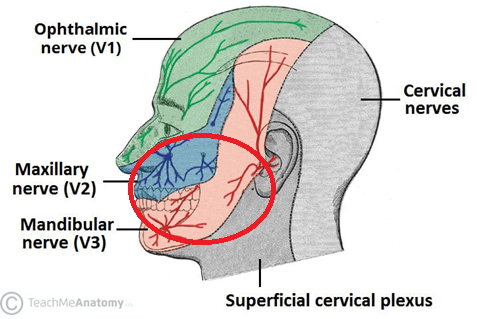

입술 헤르페스와 동시에 삼차신경통 양상, 한쪽 V2/3 영역, 항바이러스제 투약후 금방 호전됨, 같은날 진료본 치과의 해석은? - 동대문구 답십리, 전농동, 우리안애 우리안愛 내과

50대 초반 여자 대상포진 상담? 으로 접수 본인도 인지하고 있어 얘기 (가끔 이 소견을 빼놓고 얘기를 시작하는 경우가 있다.), 오른쪽 입술 아래쪽 외측; 수포 확인 오른쪽 관자놀이/턱/귀; 한번씩 찌릿 (귀), 눈깜빡이면 눈아랫쪽 (상악골~광대) 이 찌릿하다 (V2/V3 영역), 만져도 그런듯.. ; 1st episode 과거에 대상포진? 있었다고 하며.. 이렇게 얘기하는 경우가 거의 없는데, 단순포진인데 비슷한 신경분포에 신경통 양상의 증상이 있는 모습이다. 구강 헤르페스 이후 삼차신경통? 약하지만 과감각으로 CN V, 제5뇌신경 분포에, 양측으로 https://blog.naver.com/ejercicio/223866719807 V 신경보다는 한단계 낮은 근접 신경영역 (C2~3) 의 증상을 호소했던 경우 https://blog.naver.com/ejercicio/223620030505 Painful neuralgia of C2-